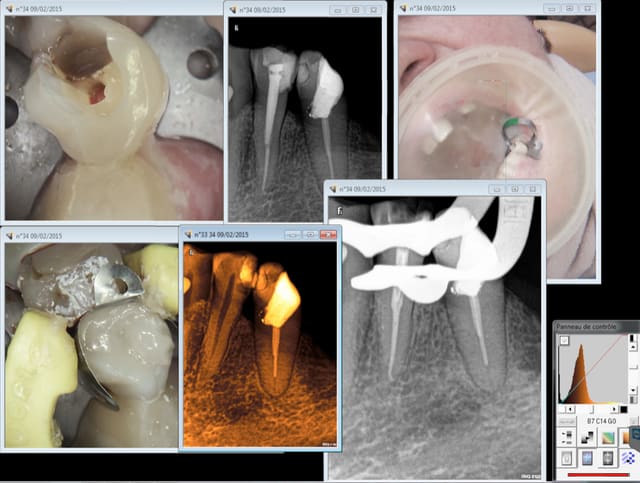

chicot29

La carestream KODAK est pas mal. Ca aide un peu pour la communication avec le patient.

Redoutable aussi en cas d'un éventuel problème juridique. -)))))

A la radio les patients pigent que dalle ( et meme certains praticiens apparemment vu l'endo de qualité une fois de plus sur la 16 ) . Une photo bien zoomée les éclairent.

Capture d e cran 2015 02 10 09.52 - Eugenol